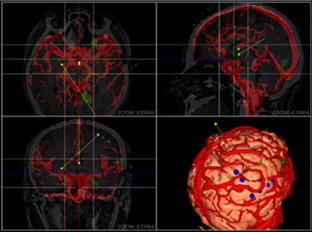

同方鼎欣專業(yè)影像產(chǎn)品群是直接面向神經(jīng)外科、骨科、血管分析等臨床科室的輔助診療、手術(shù)計劃、分析的解決方案,系統(tǒng)整合了醫(yī)療影像的導入、二維閱片、三維重建、序列配準融合、自動分割、自動計算、手術(shù)計劃等一系列功能。充分滿足了臨床科室的專業(yè)需求,提供了完整、強大、可靠、方便的工具平臺。